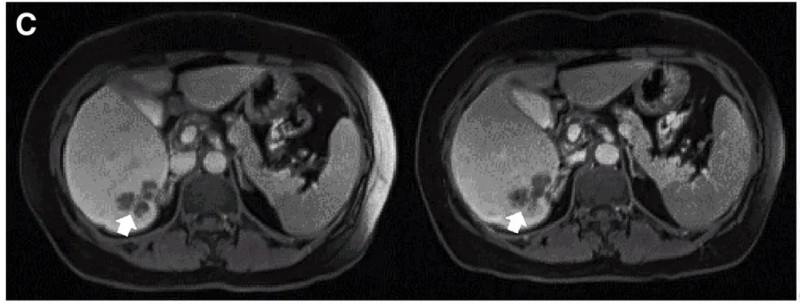

患者C01:33岁女性,诊断为弥漫大B细胞淋巴瘤,三线全身化疗后接受同情用药。结果显示:输注新型CAR-T细胞1个月后,达完全缓解(CR),并在3个月、6个月时维持CR(详见下图)。

▲图源“Cell”,版权归原作者所有,如无意中侵犯了知识产权,请联系我们删除